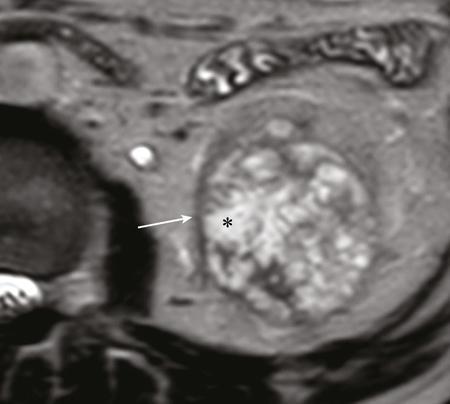

IMAGING OF RENAL MALIGNANCIES IN ADULTS Aparna Katdare, Palak Bhavesh Popat, Nilesh P. Sable, Ganesh Bakshi, Suyash Kulkarni Detection of renal masses has increased remarkably in recent times owing to wide-spread use of cross-sectional imaging. Imaging plays an important role in characterizing renal masses and is indispensable in treatment planning in renal malignancies. The most commonly encountered malignant renal masses in practice include renal cell carcinoma (RCC), urothelial carcinoma, lymphoma and metastases. Urothelial carcinoma and lymphoma have been covered in detail in separate chapters. RCC constitutes nearly 90% of all renal malignancies with a higher incidence in North America and Europe than India, Africa and China. With an increase in the number of cross-sectional studies performed, especially in Western population, the incidental diagnosis of RCC has increased in recent times, with such incidentally diagnosed lesions presenting at earlier stages with better prognosis and reduced rates of recurrence. The median age of presentation of RCC is 64 years according to the Surveillance, Epidemiology and End Results (SEER) program database and almost a decade earlier in Indian population, with a definite increasing risk of RCC with increasing age. Males are affected about 2–3.5 times more than females. In the Indian population, patients have been seen to present at a later stage as compared to the Western population. Amongst the various postulated risk factors, there is convincing evidence that smoking, hypertension, obesity and acquired renal cystic disease increase the risk of RCC. Alcohol intake and physical activity have been found to be associated with reduced risk of RCC. Trichloroethylene and cadmium exposure have been postulated as likely causes as well. Two to four per cent of RCCs are hereditary, with association of various genetic disorders such as Von Hippel Lindau (VHL) syndrome, hereditary papillary renal carcinoma, hereditary leiomyomatosis RCC, Birt-Hogg-Dube syndrome, chromosome 3 translocation and tuberous sclerosis (TCS1, TCS2). The WHO classification of 2016 (Table 11.25.1.1) stratifies tumours of the kidney into different subtypes based on cytoplasmic and architectural features, tumour location, background renal disease and molecular alterations. Clear cell renal cell carcinoma Multilocular cystic renal neoplasm of low malignant potential Papillary renal cell carcinoma Hereditary leiomyomatosis and renal cell carcinoma-associated renal cell carcinoma Chromophobe renal cell carcinoma Collecting duct carcinoma Renal medullary carcinoma MiT family translocation renal cell carcinomas Succinate dehydrogenase-deficient renal carcinoma Mucinous tubular and spindle cell carcinoma Tubulocystic renal cell carcinoma Acquired cystic disease-associated renal cell carcinoma Clear cell papillary renal cell carcinoma Renal cell carcinoma, unclassified Papillary adenoma Oncocytoma 8310/3 8316/1a 8260/3 8311/3* 8317/3 8319/3 8510/3a 8311/3a 8311/3 8480/3a 8316/3a 8316/3 8323/1 8312/3 8260/0 8290/0 Metanephric adenoma Metanephric adenofibroma Metanephric stromal tumour 8325/0 9013/0 8935/1 Nephrogenic rests Nephroblastoma Cystic partially differentiated nephroblastoma Paediatric cystic nephroma 8960/3 8959/1 8959/0 Clear cell sarcoma Rhabdoid tumour Congenital mesoblastic nephroma Ossifying renal tumour of infancy 8964/3 8963/3 8960/1 8967/0 Leiomyosarcoma Angiosarcoma Rhabdomyosarcoma Osteosarcoma Synovial sarcoma Ewing sarcoma Angiomyolipoma Epithelioid angiomyolipoma Leiomyoma Haemangioma Lymphangioma Haemangioblastoma Juxtaglomerular cell tumour Renomedullary interstitial cell tumour Schwannoma Solitary fibrous tumour 8890/3 9120/3 8900/3 9180/3 9040/3 9364/3 8860/0 8860/1a 8890/0 9120/0 9170/0 9161/1 8361/0 8966/0 9560/0 8815/1 Cystic nephroma Mixed epithelial and stromal tumour 8959/0 8959/0 Well-differentiated neuroendocrine tumour Large cell neuroendocrine carcinoma Small cell neuroendocrine carcinoma Phaeochromocytoma 8240/3 8013/3 8041/3 8700/0 Renal haematopoietic neoplasms Germ cell tumours The morphology codes are from the International Classification of Diseases for Oncology (ICD-O) {917A}, Behaviour is coded/0 for benign tumours; /1 for unspecified, borderline or uncertain behaviour; /2 for carcinoma in situ and grade III intraepithelial neoplasia; and /3 for malignant tumours. The classification is modified from the previous WHO classification (756A), taking into account changes in our understanding of these lesions. aNew code approved by the IARC/WHO Committee for ICD-O. Of these, the most common entity is the clear cell subtype, while papillary and chromophobe subtypes are less common. The different subtypes show varied biological behaviour, treatment response and prognosis. The 2017 guidelines by American Urological Association (AUA) as well as 2019 guidelines by European Society of Medical Oncology (ESMO) recommend multiphase cross-sectional imaging by either CT or MRI for renal mass characterization and staging. AUA 2017 guidelines recommend renal mass characterization on the basis of tumour complexity, contrast enhancement and presence or absence of fat. MRI has an upper hand over CT in characterizing subtle mass enhancement, cystic lesions and lesions less than 2 cm. ESMO recommends contrast-enhanced CT study of the chest, abdomen and pelvis for renal mass staging. Bone scan and brain CT or MRI can be considered if indicated by clinical or laboratory investigations. For characterization of renal masses, a multiphase CT or MRI study is recommended. CT study constitutes an unenhanced study followed by contrast injection and acquisition of corticomedullary phase at 40 seconds, nephrographic phase at around 100 seconds and delayed phase at around 5 minutes. MRI protocol includes T2-weighted single-shot fast spin-echo 2D sequences, axial T1-weighted 2D sequence with in-phase and opposed-phase gradient echo imaging, precontrast and postcontrast imaging with a 3D T1-weighted spoiled gradient recalled sequences in corticomedullary phase at 30 seconds, nephrographic phase at 100 seconds, 180–210 seconds and delayed phase imaging at 5 minutes and diffusion-weighted imaging with multiple b-values 0–50, 400–500 and 800–1000 s/mm2. The ACR White Paper on CT imaging of incidental renal mass recommends using the following descriptors for characterizing renal masses: Given the prognostic implications, it is worthwhile for radiologists to know the imaging features that may help discriminate between the common histological subtypes of RCC on various imaging modalities. This is the most common histological type of RCC, accounting for about 70% of cases. These are exophytic tumours with a heterogeneous appearance due to the presence of necrosis, intratumoural haemorrhage, cystic components with septations and calcific foci and hence have a more heterogeneous appearance on cross-sectional imaging than the other subtypes (Fig. 11.25.1.1). Necrosis is seen more often in larger masses and higher tumour grades (Fig. 11.25.1.2). On CT, depending on the tumour composition, these are seen as heterogeneous lesions, show marked contrast enhancement in the corticomedullary phase with washout on nephrogenic phase (Fig. 11.25.1.2). On MRI, these characteristically show high signal intensity on T2W sequences (Fig. 11.25.1.3). The presence of intracytoplasmic fat in the clear cells of the tumour is reflected in the loss of signal in opposed phase images on chemical shift imaging, which is seen in nearly 60% of these tumours. A pseudocapsule may be seen, which is best appreciated on T2-weighted imaging on MRI; the presence of a pseudocapsule has a high negative predictive value for perinephric extension (Figs. 11.25.1.3 and 11.25.1.4). Conversely, larger tumours with higher grades often have interrupted pseudocapsule and hence tend to be irregular, spread into the perinephric fat with renal vein and inferior vena cava (IVC) invasion (Figs. 11.25.1.5 and 11.25.1.6). On diffusion-weighted imaging, clear cell RCCs have been seen to have higher ADC values than nonclear cell RCCs, and lower-grade tumours have been seen to have higher ADC values than higher-grade tumours. The clear cell variant has worse prognosis than the papillary and chromophobe subtypes, presenting at a more advanced stage and being more likely to recur or metastasize (Fig. 11.25.1.7), with lower 5-year survival rates at 44%–69% as compared to 78%–92% for the other two. Papillary RCC comprises about 10%–15% of RCCs. These are slow-growing tumours and hence are well-marginated in contrast to clear cell RCC. As they are hypovascular, their enhancement on CT is significantly less than clear cell RCC (Fig. 11.25.1.8). These show characteristically low signal on T2W images on MRI (Fig. 11.25.1.9). Intracytoplasmic or macroscopic fat is less often seen on MRI imaging as compared to the clear cell variants. Larger tumours tend to be more heterogeneous (Fig. 11.25.1.10). These tumours may sometimes show cystic appearances, mural projections or blood degradation products. Calcifications are more common in papillary variants than clear cell RCC. Multifocality and bilaterality are also more common in these tumours than clear cell variants. These account for about 5% of RCCs. These are less aggressive, more homogeneous and hypovascular lesions than clear cell variants, with intensity of contrast enhancement on cross-sectional imaging being midway between clear cell and papillary variants. They show low to intermediate T2 signals on MRI. A characteristic feature is the presence of a central scar and spoke-wheel enhancement, the latter being a histopathological and imaging similarity between these tumours and oncocytoma (Fig. 11.25.1.11). Other subtypes of RCC are much less common but some may show distinct imaging findings. Multilocular cystic RCCs have excellent prognosis and lack mural nodules within the cystic components, unlike clear cell RCCs with cystic degeneration which show mural nodules. Collecting duct carcinomas, on the other hand, are aggressive tumours with poor prognosis and have medullary origin, and therefore appear similar to transitional cell carcinomas on imaging. Medullary RCCs are associated with sickle cell disease and sickle cell trait and are seen as infiltrating intracalyceal obstructive lesions with associated nodal disease. The imaging work-up of a suspected RCC is aimed at: Localized renal cancer is defined as a disease confined to the renal capsule and refers mainly to stage I and II disease. Nearly 70% of RCCs, especially the lower-stage lesions, are incidentally diagnosed on cross-sectional imaging. Also, amongst incidentally diagnosed renal lesions less than 4 cm in size, about 20% turn out to be benign on histopathology. Asymptomatic incidentally diagnosed small renal masses have an indolent course and better prognosis. Nephron-sparing surgery (NSS) has gathered momentum in recent years due to promising results and prognoses in small lesions. The 2017 AUA guidelines for localized renal masses describe restricted and well-defined indications for radical nephrectomy, bigger role of nephron-sparing procedures such as partial nephrectomy, tumour enucleation and thermal ablation, as well as increasing role for biopsy as well as active surveillance of such lesions. Hence, imaging findings in these lesions become critical in charting management of these patients. The imaging features of common histopathological subtypes of RCCs have already been discussed above. Signal intensity on T2W images and corticomedullary phase enhancement have been seen to be independent predictors of clear cell and papillary RCCs. Further, T2 signal homogeneity can be a predictor for slower growth rate. Hence, in general, multiparametric MRI studies have been shown to be effective in small renal mass characterization and can subsequently guide decisions regarding biopsy, surgery or surveillance. CT is a good alternative in patients with contraindication to MRI. For cystic renal lesions, the Bosniak classification, which stratifies the risk of neoplasia in cystic renal lesions based on the complexity of their appearance (wall thickness, septations, solid component), can be used effectively to decide further course of management. The Bosniak classification originally applies to CT findings but can logically be extrapolated to MRI, USG and Contrast Enhanced Ultrasound (CEUS) as well. Bosniak I and II cysts are benign while Bosniak IIF, III and IV cysts show progressively increasing risk of neoplasia. Given the more indolent course of cystic RCCs as compared to solid lesions and possible complications of interventions, lately there has been a case for even the type III and IV cysts, which previously would be operated, to be followed up, especially if patient has existing comorbidities or if the solid component is minimal. Initial follow-up would be at 6 months, followed by annual imaging. AUA 2017 guidelines recommend considering renal mass biopsy if haematologic, metastatic, inflammatory or infectious aetiology is suspected. Once the need for surgery is established in a localized disease, NSS may be considered for stage Ia and Ib disease. To predict perioperative outcomes in NSS, various scoring systems have been proposed for preoperative renal mass evaluation, such as R.E.N.A.L. nephrometry score, PADUA score (Preoperative aspects and dimensions used for anatomical classification), C-index method and mathematical tumour contact surface area (CSA). The popular R.E.N.A.L. nephrometry score takes into account various tumour descriptors that help decide the technical feasibility of NSS and predict surgical outcomes. These include tumour radius, exo/endophytic location, nearness to collecting system or renal sinus, anterior/posterior location and location with reference to polar lines. These descriptors need to be commented upon diligently while reporting renal masses (Table 11.25.1.4). Higher scores are seen to correlate with ischaemia time, postoperative urologic complications, higher grade and mortality. These include organ-confined tumours more than 7 cm in size, or tumours of any size which show regional nodal involvement and/or invasion of perinephric tissues but confined to Gerota’s fascia. These include renal vein and IVC invasion (luminal and mural). Generally, radical nephrectomy is recommended by the National Comprehensive Cancer Network (NCCN) in stage II and III RCCs. Both CT and MRI are effective in diagnosing locally advanced disease in RCC. The loss or interruption of pseudocapsule is seen in more infiltrative and aggressive disease and is best seen on MRI. Local infiltration may be in the form of contiguous spread to perinephric tissues or discrete deposits in perinephric fat (Fig. 11.25.1.15). IVC or renal vein invasion could be in the form of intraluminal thrombosis or invasion of the vessel wall and have implications on surgical approach and outcomes. Tumour thrombus can be distinguished from bland thrombus by confirming vascularity within the thrombus on imaging. Doppler evaluation, CEUS, CT and MRI can all be helpful for the same. MRI is better than other modalities for venous evaluation, especially for mural invasion and IVC invasion (Figs. 11.25.1.16 and 11.25.1.17). Right-sided tumours, anteroposterior IVC diameter of 2.4 cm or more at the level of renal hilum and complete IVC occlusion at this level are associated with higher risk of IVC resection. About 16% of patients with RCC have metastases at diagnosis and about 20%–30% of patients operated for local disease develop recurrence or metastases at a later date. The recurrent disease occurs most commonly within 3 years of diagnosis and uncommonly even later in young patients or large tumours. The most common sites of metastases from RCC are lungs, liver, bones, nodes, adrenals and brain. CT scan is the preferred modality for primary staging and surveillance for metastases because of its widespread availability and versatility for diagnosing bone and soft tissue lesions. MRI is preferred for looking for recurrence in postablative lesions, wherein these are seen as new enhancing lesions or show increase in the size of preexisting enhancing components. 18FFluorodeoxyglucose – Positron Emission Tomography (PET)/CT and PET/MRI may be helpful to look for metastatic disease as well. 18FSodium fluoride – PET/CT has been found to be better than CT and bone scan in detecting osseous metastases. RCC is a relatively radiation-resistant tumour, and treatment options tilt in favour of surgical procedures for localized and locally advanced diseases. For metastatic disease, post-risk assignment, the treatment has to be planned. Treatment can be offered as per size and the clinical stage.